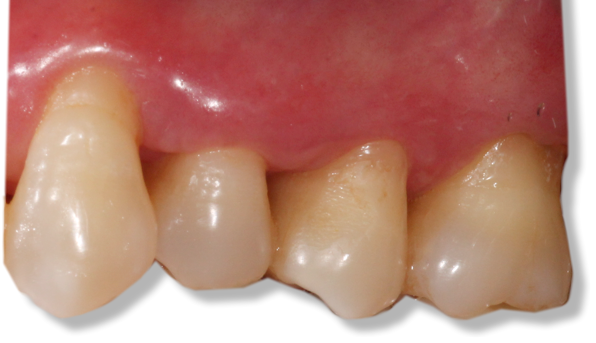

![]() | ![]() |

| Free gingival graft surgery’ to thicken gum and prevent further recession | Gum recession surgery in an aesthetic site |